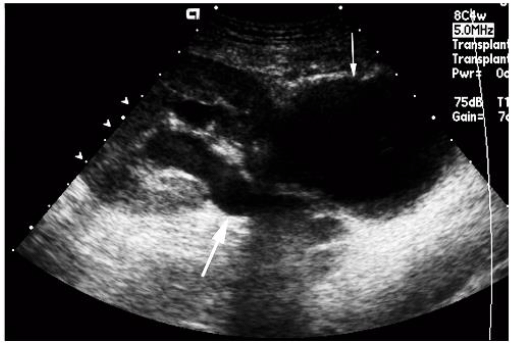

Homem de 42 anos, com história de transplante renal há três meses, se apresenta com queixa de abaulamento subjacente à cicatriz cirúrgica do enxerto na fossa ilíaca direita, sem dor ou vermelhidão local. Nega febre. Sua creatinina sérica é de 1,0 mg/dL. Uma avaliação ultrassonográfica é realizada, observando-se dilatação pielocalicial moderada no rim transplantado, assim como uma coleção subjacente à ferida operatória, conforme imagens abaixo. De acordo com a história clínica e o exame complementar, assinale a alternativa correta.